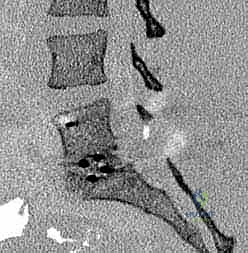

يتم وضع المريض على بطنه. يتم عمل شق جراحي دقيق في أسفل الظهر. باستخدام أجهزة الملاحة الجراحية والأشعة السينية الحية (Fluoroscopy)، يتم تحديد المستويات الفقرية المستهدفة بدقة.

الخطوة 2: إزالة الضغط العصبي (Decompression)

يقوم د. هطيف بإزالة الأجزاء العظمية الضاغطة (Laminectomy أو Facetectomy) والأربطة المتضخمة بدقة ميكروسكوبية لتحرير الأعصاب الشوكية المختنقة.

الخطوة 3: استئصال القرص التالف (Discectomy)

يتم تفريغ القرص الغضروفي التالف بالكامل، وإعداد المساحة بين الفقرتين (Endplates) لاستقبال الطعم العظمي. هذه الخطوة حاسمة لضمان التحام العظام لاحقاً.